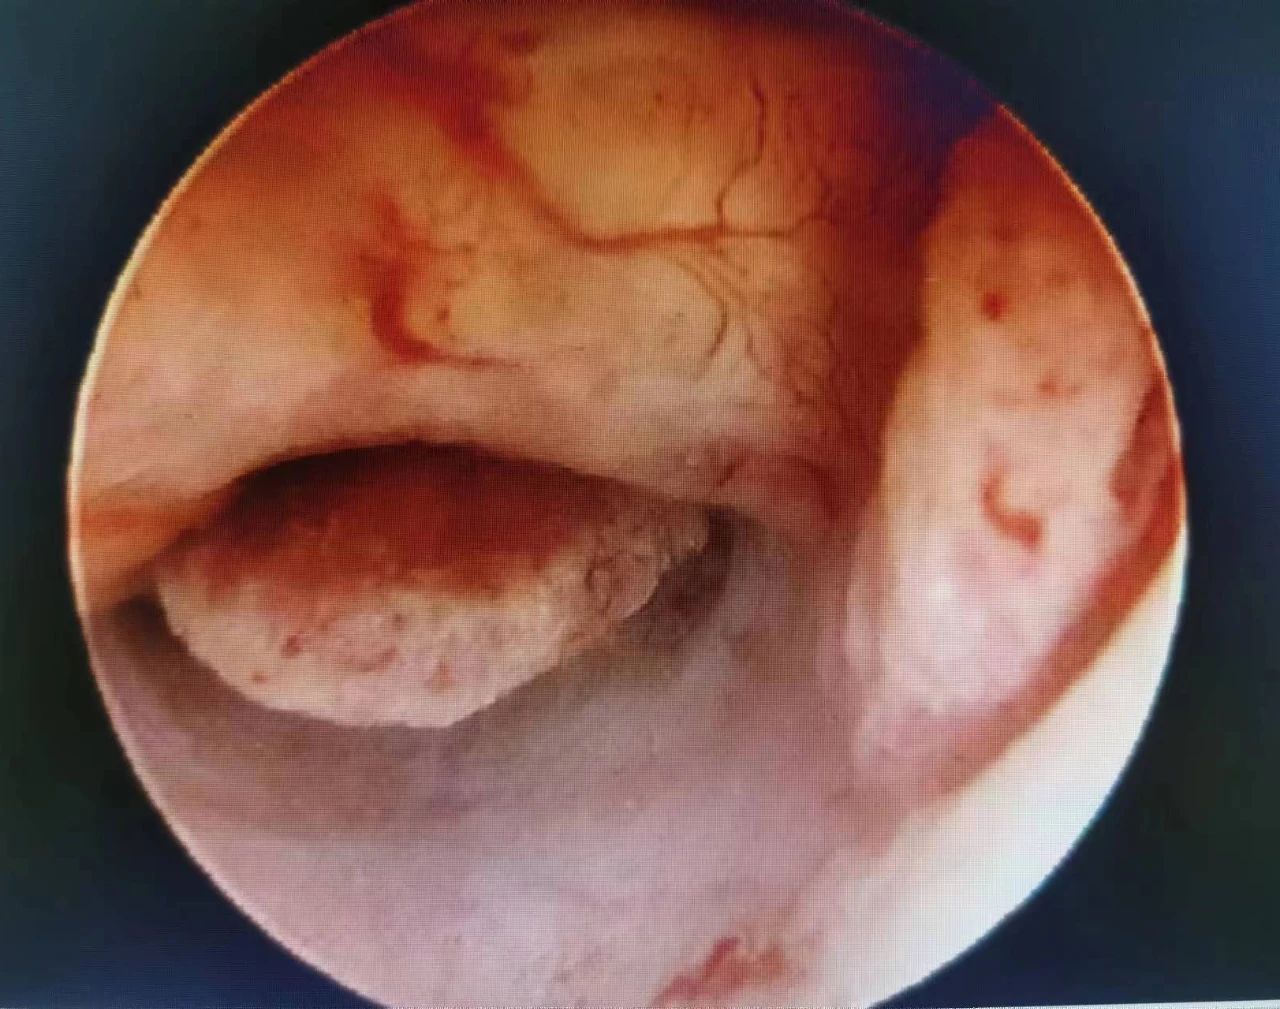

宫腔镜下可见子宫内膜息肉样增生

血管明显扩张扭曲